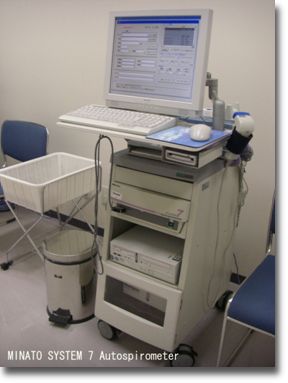

肺機能検査

口に管をくわえ、鼻をクリップで止め、鼻を使わず口で呼吸し肺の機能(肺活量・1秒量など)をみる検査です。肺気腫や喘息などの肺疾患の診断・全身麻酔手術の術前検査に必要な検査です。検査時間は5分~15分程度です。